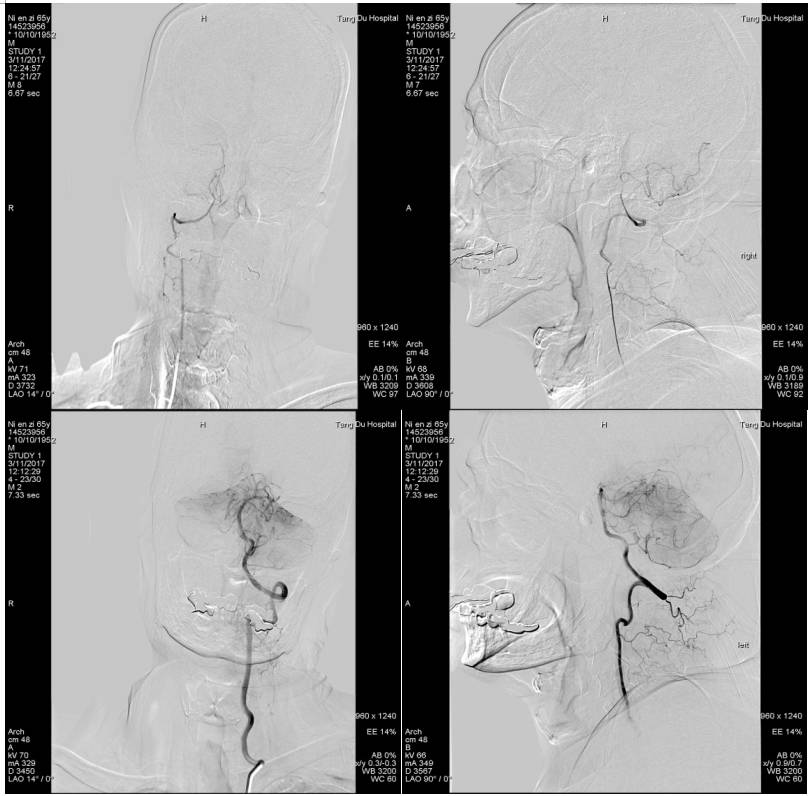

术中用微导管将支架放置狭窄部位,术中见支架Mark显影良好,释放支架5分钟,回收支架,可见支架上附着血栓。

行血管造影示:双侧大脑后动脉显影,远端血管快速充盈,TICI:3级,术毕。患者言语较前流利,可准确应答,左侧肌力恢复正常,NHISS评分1分。